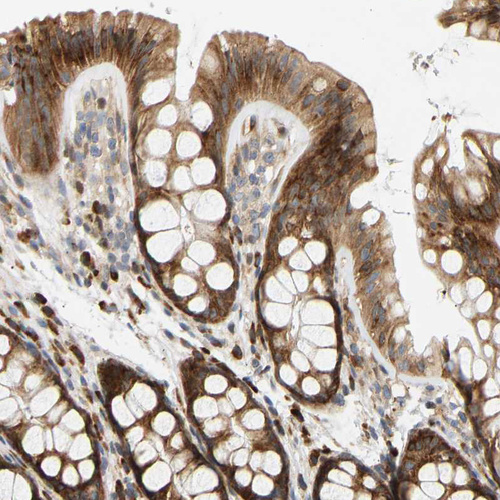

Immunohistochemical staining of human Fallopian tube shows weak to moderate cytoplasmic positivity in glandular cells.